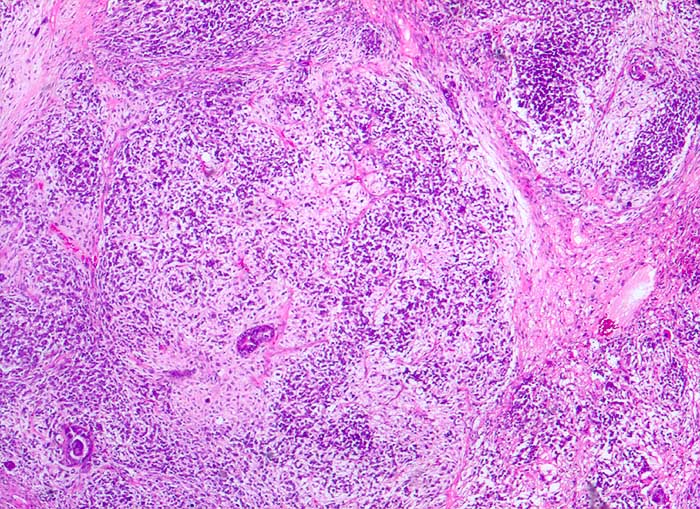

PathoPic ID 5386 - maligner Müller'scher Mischtumor des Ovars

maligner Müller'scher Mischtumor des Ovars

maligner Tumor

Ovar

Genitalorgane, weiblich

Karzinomatöse Drüsen in malignem mesenchymalem Stroma

Ovarialkarzinom

Histologie

25

71